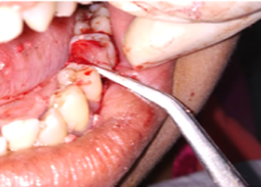

Post-OP Clinical View

Bone Graft Placement